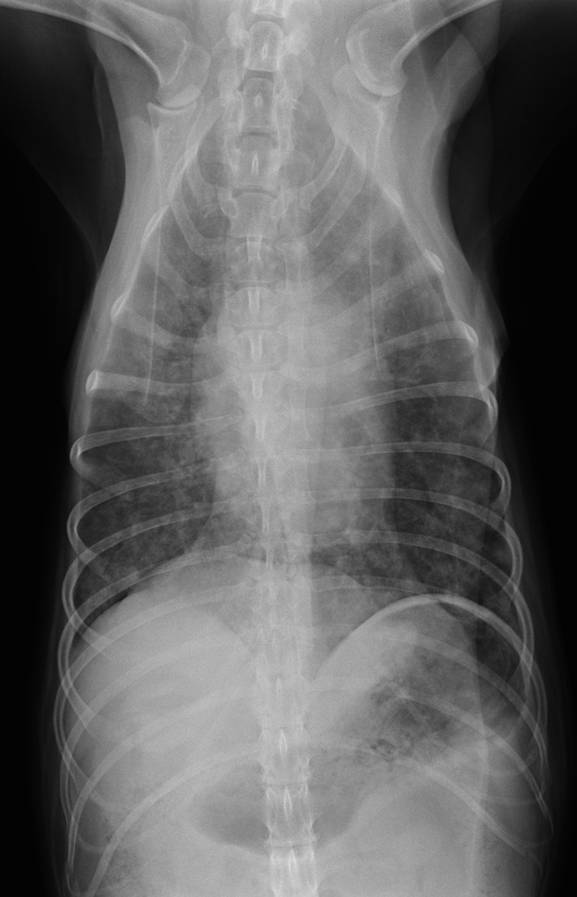

猫の鼻腔リンパ腫。

ねこちゃんで最も多い悪性腫瘍のリンパ腫がお鼻にできてしまったもの。クシャミなどの風邪症状や食欲不振、お顔の腫れで気づく場合が多いです。

他の臓器へのがん細胞の浸潤がない場合は放射線治療が最も効果的です。抗がん剤等を使用した化学療法も行われます。

case.1

初診時

左側鼻腔のX線不透過像を認める。

化学療法4週後。